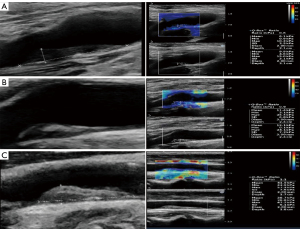

Contrast-enhanced ultrasound (CEUS) was used to assess the density, location, and diffusion direction of the contrast agent of IPN. The ulceration neovascularization in carotid plaques can be determined based on the diffusion pattern of the contrast agent (7). The way in which the contrast agent diffuses from the outer vascular membrane to the base of the atherosclerotic plaque indicates neovascularization in plaque. The location and quantity of neovascularization in the plaque and the diffusion direction of the contrast agent were observed.

The neovascularization in the plaque was graded visually as follows (8): Grade 0: no significant enhancement; Grade 1: shoulder or base enhancement; Grade 2: both shoulder and base enhancement; Grade 3: patchy enhancement toward the center; Grade 4: diffuse enhancement (see Figure 1).

Shear wave elastography was used to measure the YM values (see Figure 2). Additionally, the direction of contrast agent diffusion in the plaque was categorized as internal-external or non-internal-external (where “internal” refers to the artery lumen, and “external” refers to the outer membrane of the artery).